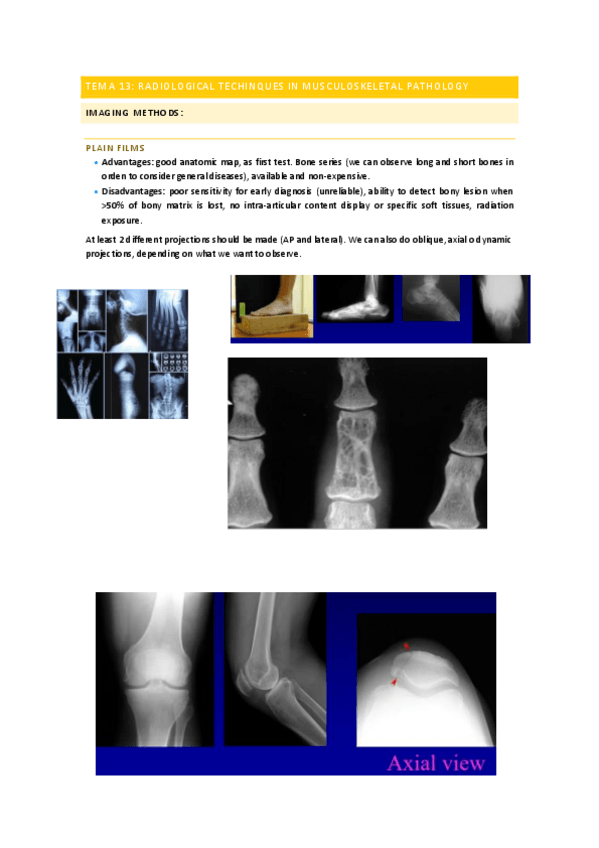

He publicado nuevos apuntes de 3º Radiología: Tema-13-Radiological-Techinques-in-musculoskeletal-pathology.pdf